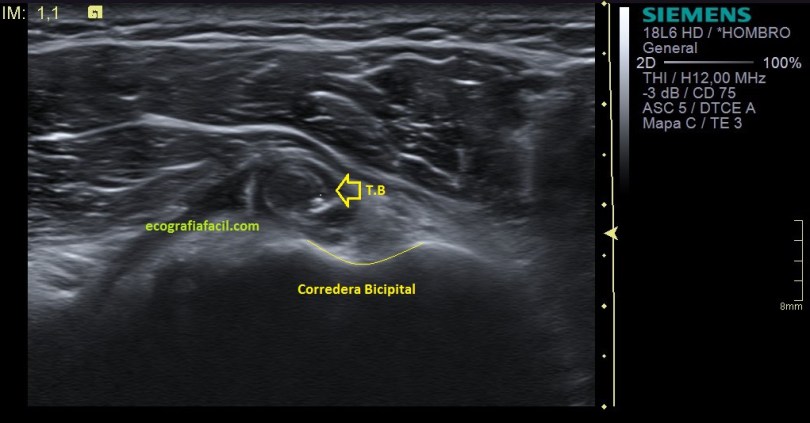

Te lo digo siempre, mucho ojo con las estructuras tendinosas y la anisotropía, sobre todo la de este tendón que pese a estar luxado tiene su ecoarquitectura conservada, pero, en la imagen número 4 puedes ver la imagen del tendón con anisotropía en eje corto y te la pongo para que compares imagen 1 y 2 e imagen 4 y te des cuenta de cómo puede variar una estructura si no realizamos la técnica correctamente. Ojo con esto ya que podemos confundir a la radióloga a la hora de hacer el informe. Combatir la anisotropía es tarea exclusiva del operador

Te marco en la imagen 4 con una línea fina amarilla la corredera bicipital por si te había costado ver la relación con el tendón desplazado y que está indicado con la flecha amarilla, pero anisotrópico.